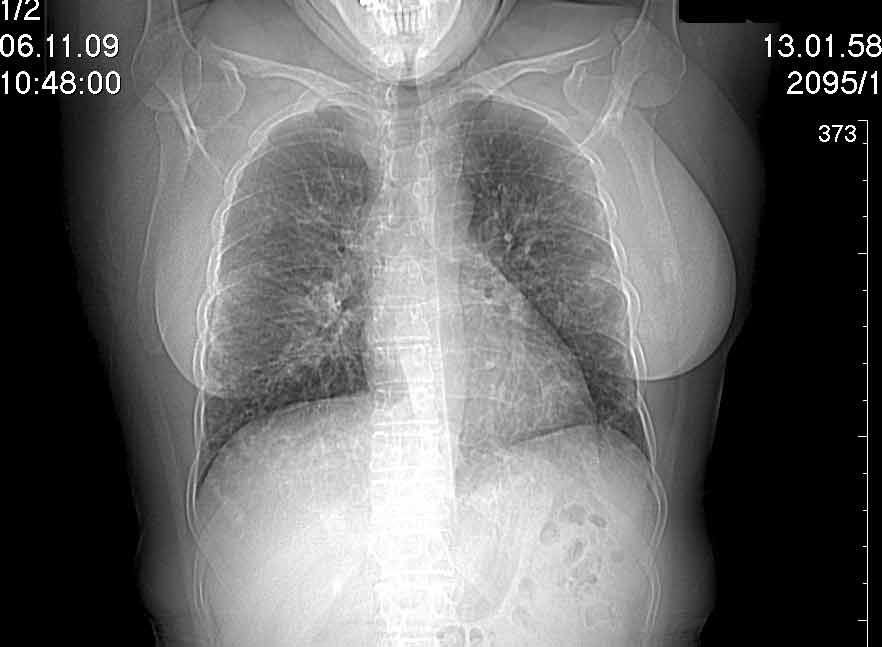

Случай №1

Женщина 50 лет.

Случай 1: изменения характерны для интерстициальной пневмонии (IIP/UIP idiopathic interstitial pneumonia/usual interstitial pneumonia); говорить о конкретной форме без открытой биопсии затруднительно.